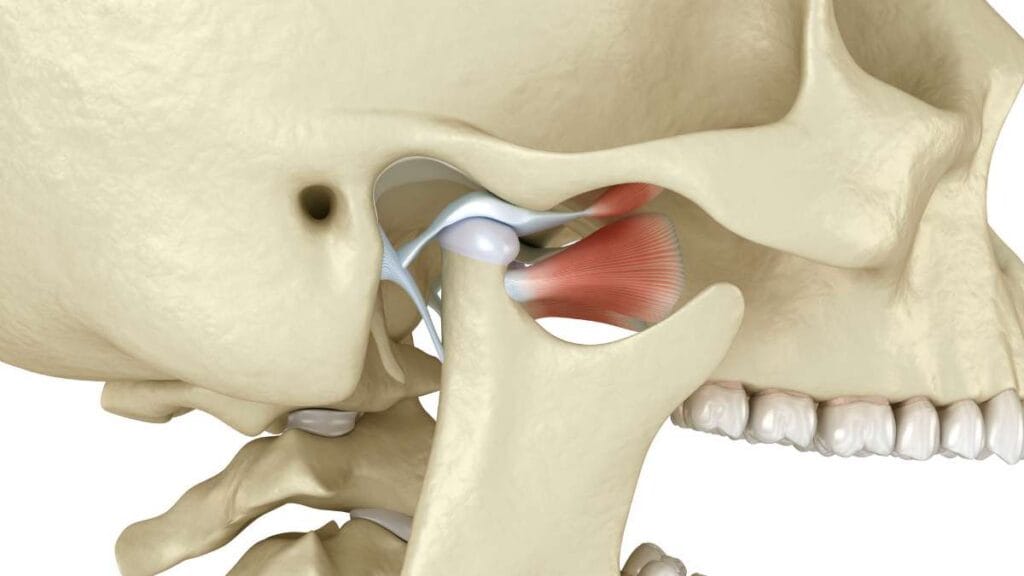

Çene ekleminin (Temporomandibular Eklem) konuşma ve çiğneme sırasındaki doğal hareket mekanizması ve eklem diskinin fonksiyonu.

Yemek yerken, esnerken ya da ağzı açıp kapatırken duyulan “klik”, “tık” veya “küt” sesi çoğu zaman masum bir alışkanlık gibi görülür. Ancak ağız açarken ses gelmesi ve çene kütlemesi, bazı olgularda eklem içindeki “disk”in normal konumundan kayması (deplasman) ile ilişkili olabilir. Disk, eklem hareketi sırasında bir ray gibi rehberlik eder; yer değiştirirse ses, takılma hissi ve zamanla ağrı görülebilir.

Ağız açıp kapama sırasında duyulan “klik” veya “tıkırtı” sesi, genellikle çene eklemi içindeki diskin (yastıkçık görevi gören kıkırdak yapı) hareket bozukluğuna işaret eder. Normalde çene kemiği ile birlikte hareket etmesi gereken bu disk, uyumsuz çalışarak öne kaydığında veya sıkıştığında bu ses oluşur. Ses tek başına her zaman acil tedavi gerektirmese de; ağrı, takılma veya ağız açıklığında kısıtlılık ile birlikte görülüyorsa mutlaka bir Çene Cerrahisi uzmanı tarafından değerlendirilmelidir.